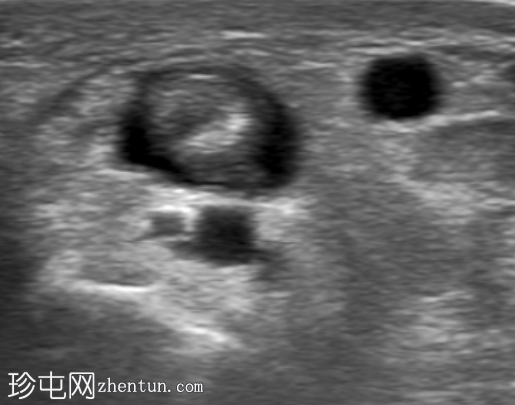

超声

横切面

第一背侧伸肌腱鞘增厚。拇长展肌 (APL) 和拇短伸肌 (EPB) 肌腱周围可见低回声液体。受累肌腱轻度增厚。未见肌腱撕裂。邻近皮质表面完整。多普勒显示轻度血流信号增多。